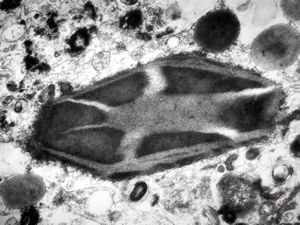

M,43y. | Auer bodies - myeloid leukemia v.s.